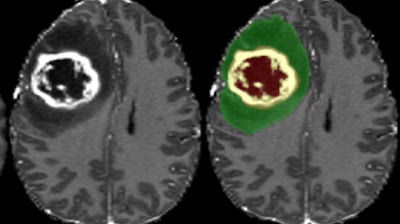

Due to the time-consuming nature of manual segmentation, this study explored potential of deep convolutional #NeuralNetworks as an alternative for fast, accurate segmentation on T1-weighted portal venous #MRI. (Moritz Gross et al.) #EuropeanRadiology 🔗 buff.ly/47K2d8y

Due to the time-consuming nature of manual segmentation, this study explored potential of deep convolutional #NeuralNetworks as an alternative for fast, accurate segmentation on T1-weighted portal venous #MRI. (Moritz Gross et al.)

🔗 buff.ly/47K2d8y